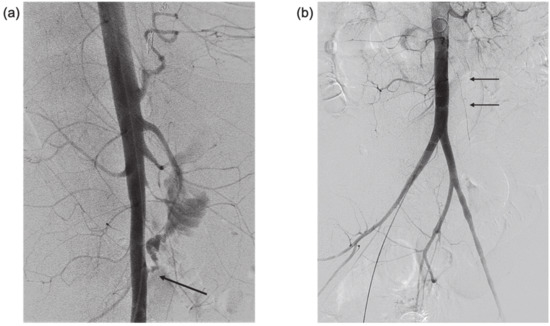

Figure 2. (a) Lateral digital subtraction aortography showing active contrast extravasation from the anterior infra renal aorta into small bowel lumen (arrow)—AEF. Note the diffuse small caliber branch vessels due to vasoconstriction in the setting of hemorrhagic shock. (b) Anterolateral aortogram after covered stent deployment in the infra renal aorta, covering the AEF (arrows). Note that extravasation is no longer seen, and there is some increase in vessel caliber due to improved hemodynamic status.

Urgent visceral angiography of celiac, superior mesenteric, left gastric, and gastroduodenal arteries was performed revealing an active source of arterial hemorrhage from a peripheral branch of the left gastric artery in the area of the gastric fundus, managed by selective coil embolization. Despite embolization, severe hematemesis and hematochezia continued, causing persistent hemodynamic instability and prompting the performance of a lateral abdominal aortography, which demonstrated active extravasation of blood into the intestine, diagnostic of an aorto-duodenal fistula (Figure 2a). Temporary balloon occlusion of the aorta was performed to stabilize the patient and control the hemorrhage. The fistula was then closed using a balloon-expandable covered stent (BeGraft, Bentley Innomed GmbH, Hechingen, Germany) at the site of the defect in the aortic wall, with immediate hemodynamic stabilization (Figure 2b). During the entire procedure, the patient received aggressive blood component support to prevent exsanguination, with 27 units of PRBC (Packed Red Blood Cells), 15 units of platelets, 22 units of FFP (Fresh Frozen Plasma) and 20 units of Cryoprecipitate administered over 3 h, in compliance with the institutional massive transfusion protocol (1PRBC:1FFP:1Platlet).